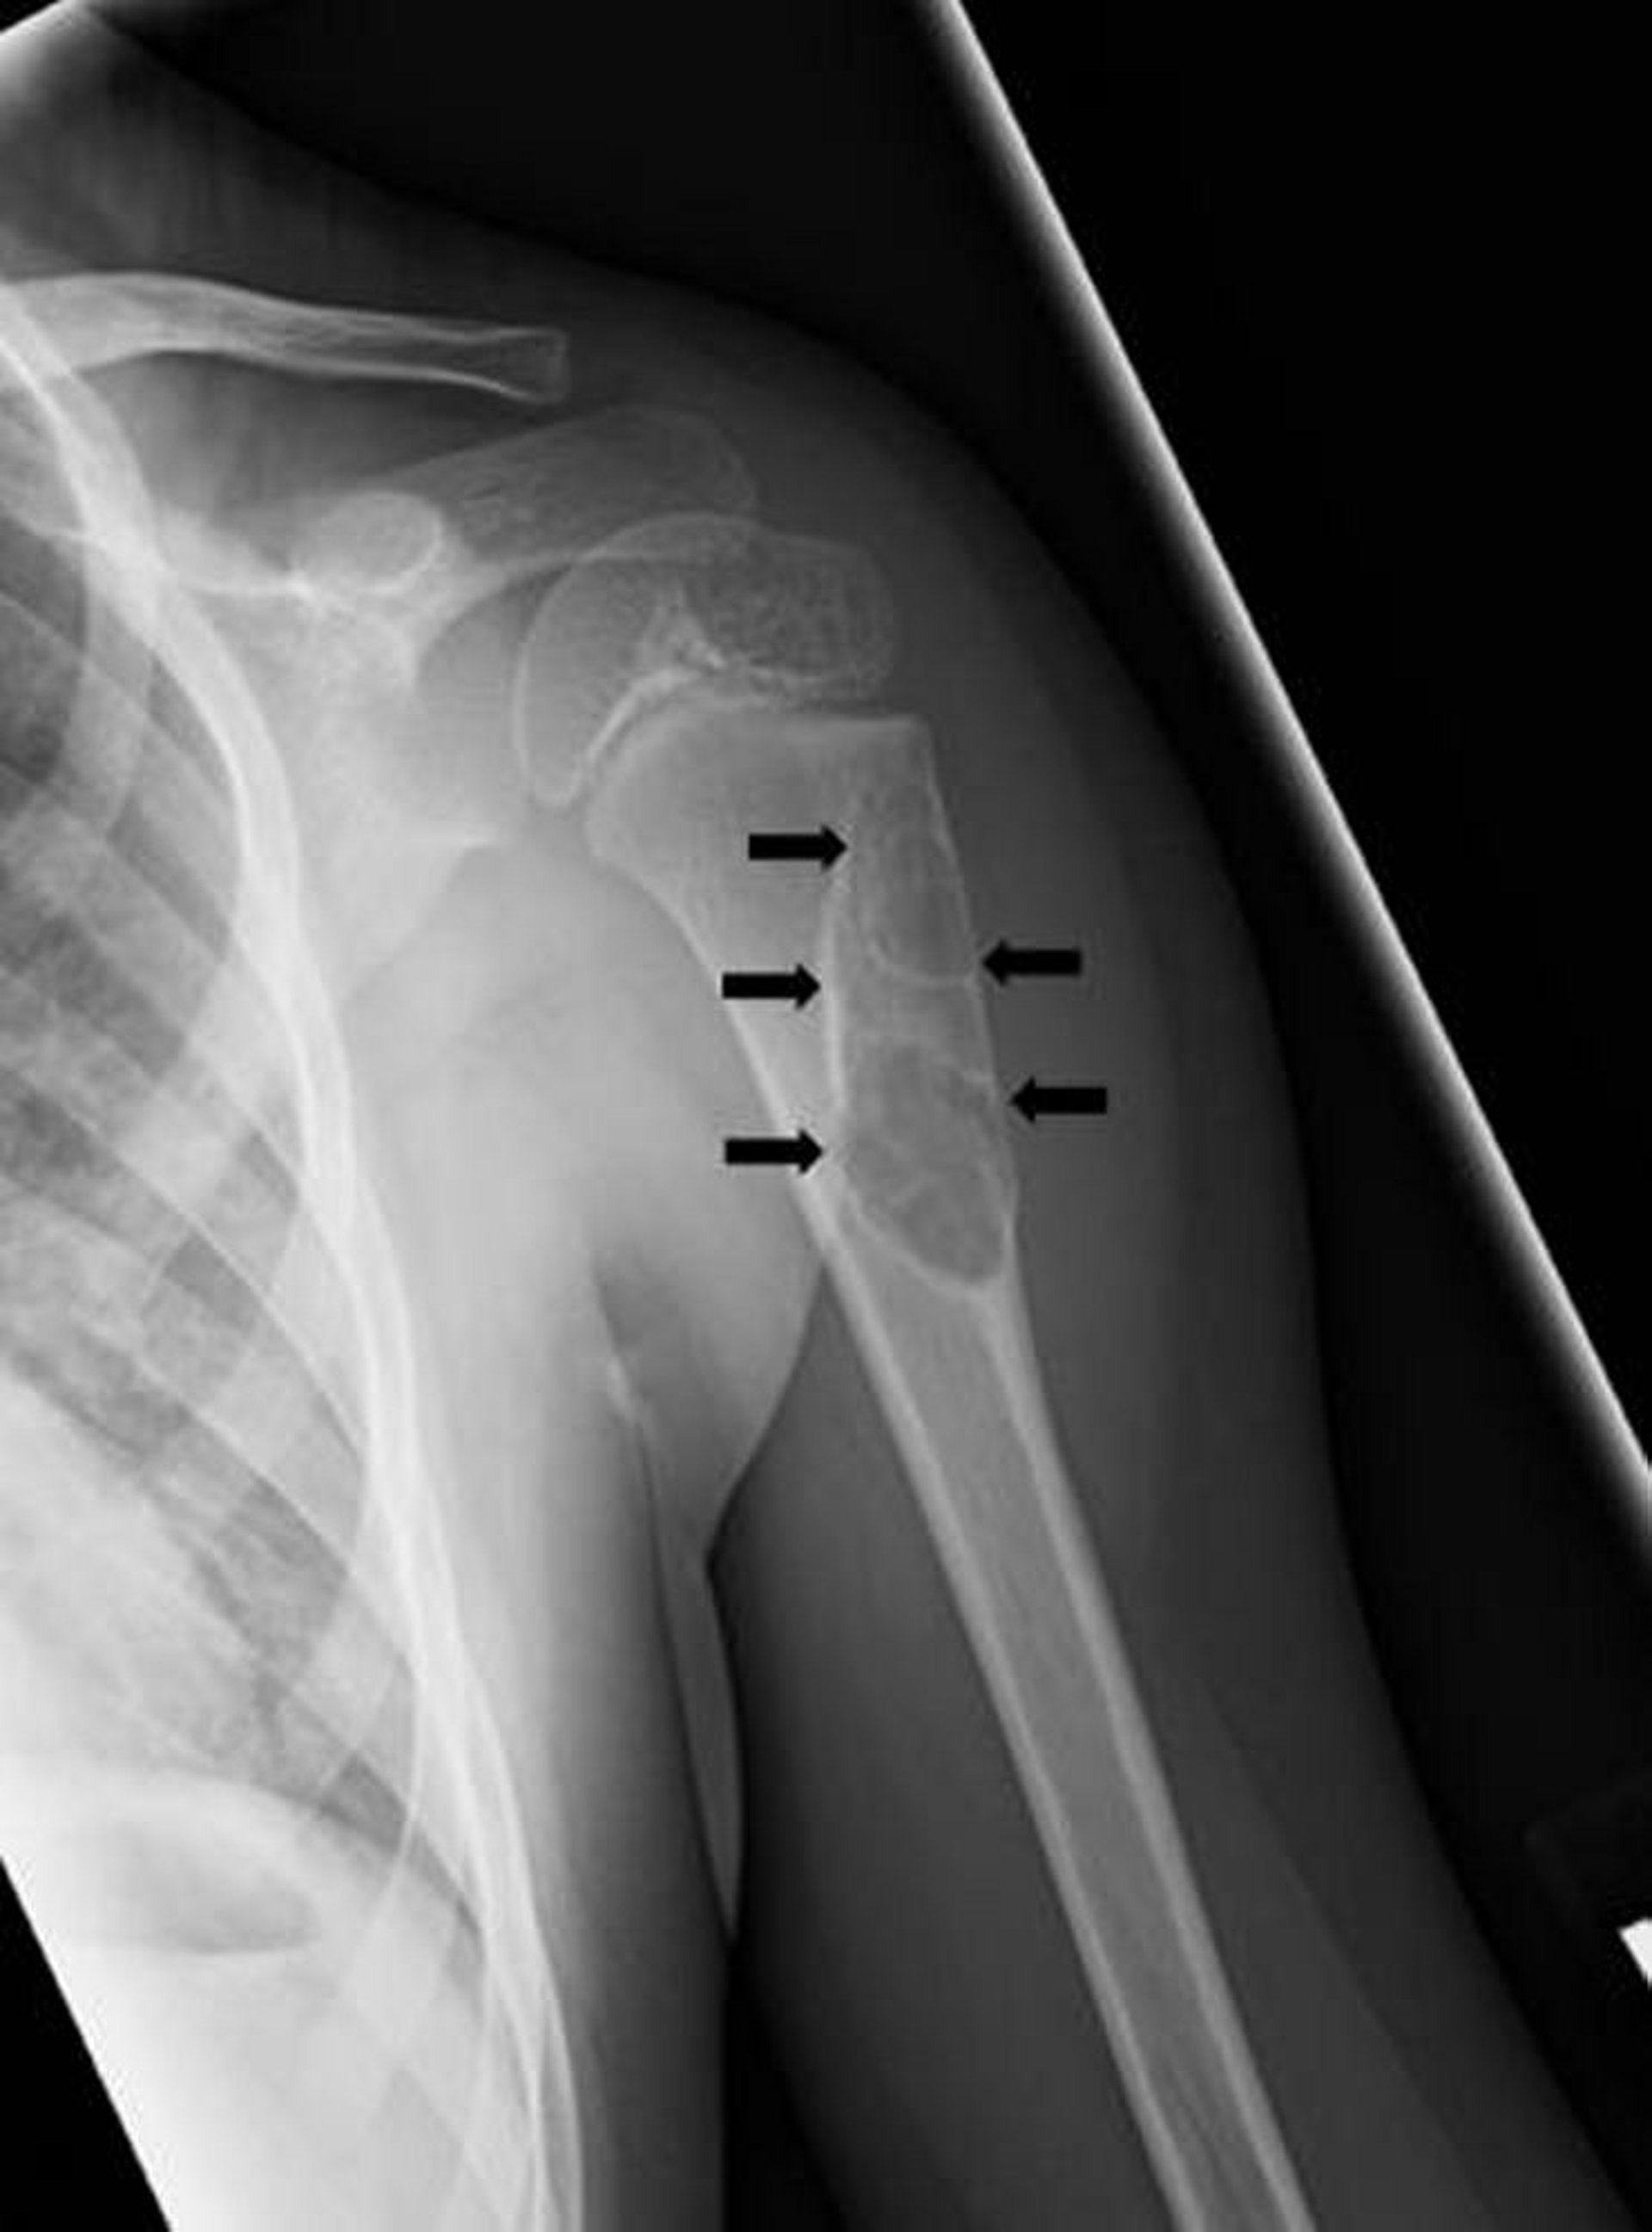

Однокамерная костная киста

На этой рентгенограмме показана простая однокамерная костная киста (стрелки) в плечевой кости.

Изображение любезно предоставлено д-ром Майклом Дж. Джойсом (Michael J. Joyce) и д-ром Хаканом Иласланом (Hakan Ilaslan).